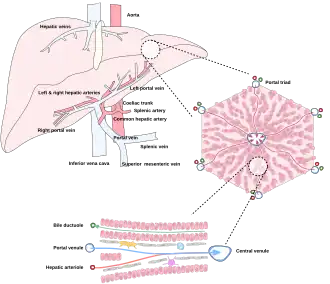

Microscopically, each liver lobe is seen to be made up of hepatic lobules. The lobules are roughly hexagonal, and consist of plates of hepatocytes, and sinusoids radiating from a central vein towards an imaginary perimeter of interlobular portal triads.[24] The central vein joins to the hepatic vein to carry blood out from the liver. A distinctive component of a lobule is the portal triad, which can be found running along each of the lobule's corners. The portal triad consists of the hepatic artery, the portal vein, and the common bile duct.[25] The triad may be seen on a liver ultrasound, as a Mickey Mouse sign with the portal vein as the head, and the hepatic artery, and the common bile duct as the ears.[26]

Histology, the study of microscopic anatomy, shows two major types of liver cell: parenchymal cells and nonparenchymal cells. About 70–85% of the liver volume is occupied by parenchymal hepatocytes. Nonparenchymal cells constitute 40% of the total number of liver cells but only 6.5% of its volume.[27] The liver sinusoids are lined with two types of cell, sinusoidal endothelial cells, and phagocytic Kupffer cells.[28] Hepatic stellate cells are nonparenchymal cells found in the perisinusoidal space, between a sinusoid and a hepatocyte.[27] Additionally, intrahepatic lymphocytes are often present in the sinusoidal lumen.[27]

-

Microscopic anatomy of the liver -

Types of capillaries–sinusoid on right -

The liver and its veins -

Diagram of liver, lobule, and portal tract and their inter-relations